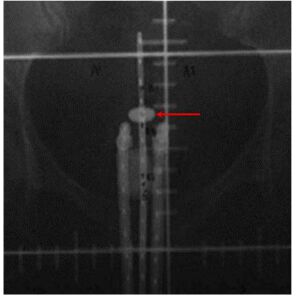

55.子宮頸癌病人接受HDR治療,連管放置好之後拍攝的X光片如圖所示,如果醫師裝置與固定的非常恰當,病人也沒亂動,則圖中箭號所指示之白色盤狀物對應到的生理組織為:(A)陰道側穹窿(lateral vaginal fornix)(B)外子宮頸口(external cervical os)(C)內子宮頸口(internal cervical os)(D)子宮體(uterus corpus)